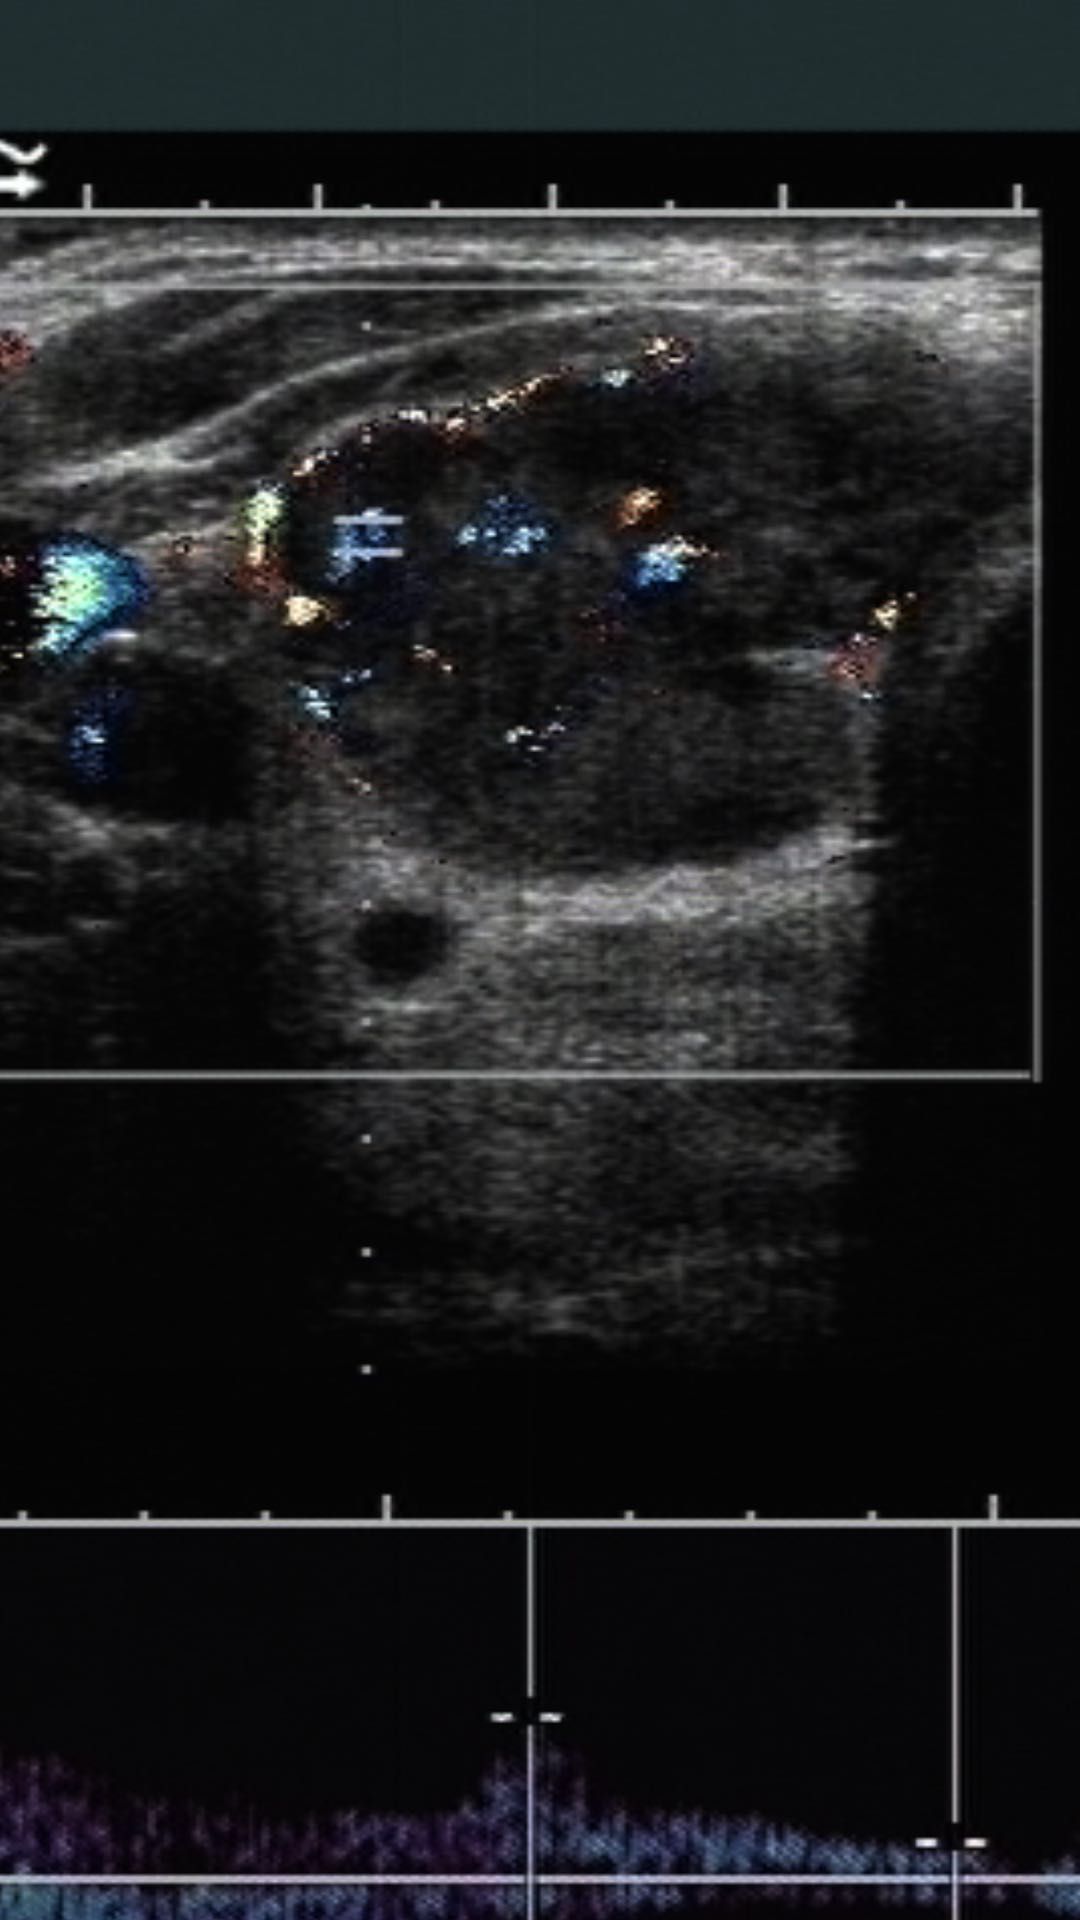

甲状腺多普勒超声图像可显示血管增生的复杂结节

图片尺寸773x526